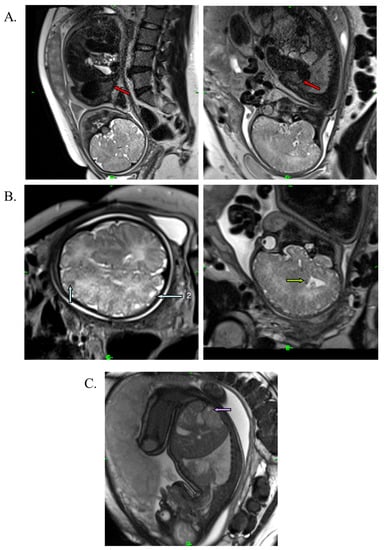

A medical team consisting of a cardiologist, clinical geneticist, obstetrician, and neonatologist decided to start oral immunosuppressant therapy for the mother (everolimus; Votubia). The goal of the treatment was to reduce the size of the rhabdomyoma, which lasted for five weeks. Oral everolimus was given daily. An initial dose of 10 mg/day everolimus was administered. The dose was adjusted to 5 mg/day from day 10 to set the 5–15 ng/mL target trough level (see Table S1). Blood values, including hemoglobin, leukocytes, leukocyte differentiation, thrombocytes, and CRP, were monitored during the treatment. All laboratory parameters were within the normal range. Everolimus reduced the size of the rhabdomyoma by almost half (20 × 20 × 33 mm) (Figure 3A). Everolimus was discontinued on day 36, two weeks before the scheduled cesarean section, to avoid complications and pre- and postnatal infection. The fetus and mother did not experience adverse events during the entire length of the treatment. Fetal MRI performed during the 38th week of gestation also revealed renal cysts in the fetus (Figure 3C).

The male infant was born at term by caesarean section with a birth weight of 3700 g (+0.67 SD), birth length of 52 cm (+1.11 SD) and a head circumference of 35 cm (+0.42 SD). This was the mother’s fourth pregnancy (G3, P1). The Apgar score was 9/10. Standard deviations (SD) for birth measurements were calculated using WHO standards [30]. After birth, the boy was monitored in a perinatal intensive care unit for one week. His laboratory parameters were normal. Cardiological examination revealed rhabdomyoma and mitral insufficiency, and the abdominal ultrasound examination suggested angiomyolipoma in the kidneys. The MRI performed at 2 months of age confirmed the findings of the perinatal examinations (Figure 4A). The MRI additionally revealed white-matter radial migration lines, presenting a straight band and nonspecific conglomerate foci (Figure 4B).

Figure 3. T2-weighted MRI image of the fetus at the 38th week of gestation. (A) Red arrows show cardiac rhabdomyoma in reduced size (20 × 20 × 33 mm). (B) Blue arrows show cortical tuber in the gyral core (2), and green arrows represent subependymal nodule in the brain. (C) Purple arrow shows the renal cyst.

Figure 4. T1-weighted axial MRI image of the brain and T2-weighted sagittal MRI image of the heart at 2 months of age. (A) Red arrows represent cardiac rhabdomyoma. (B) Blue arrows show cortical tubers in the sulcal island (1) and in the gyral core (2); green arrow represents a subependymal nodule. Brown and yellow arrows show white-matter radial migration lines: straight band (brown), nonspecific conglomerate foci (yellow).